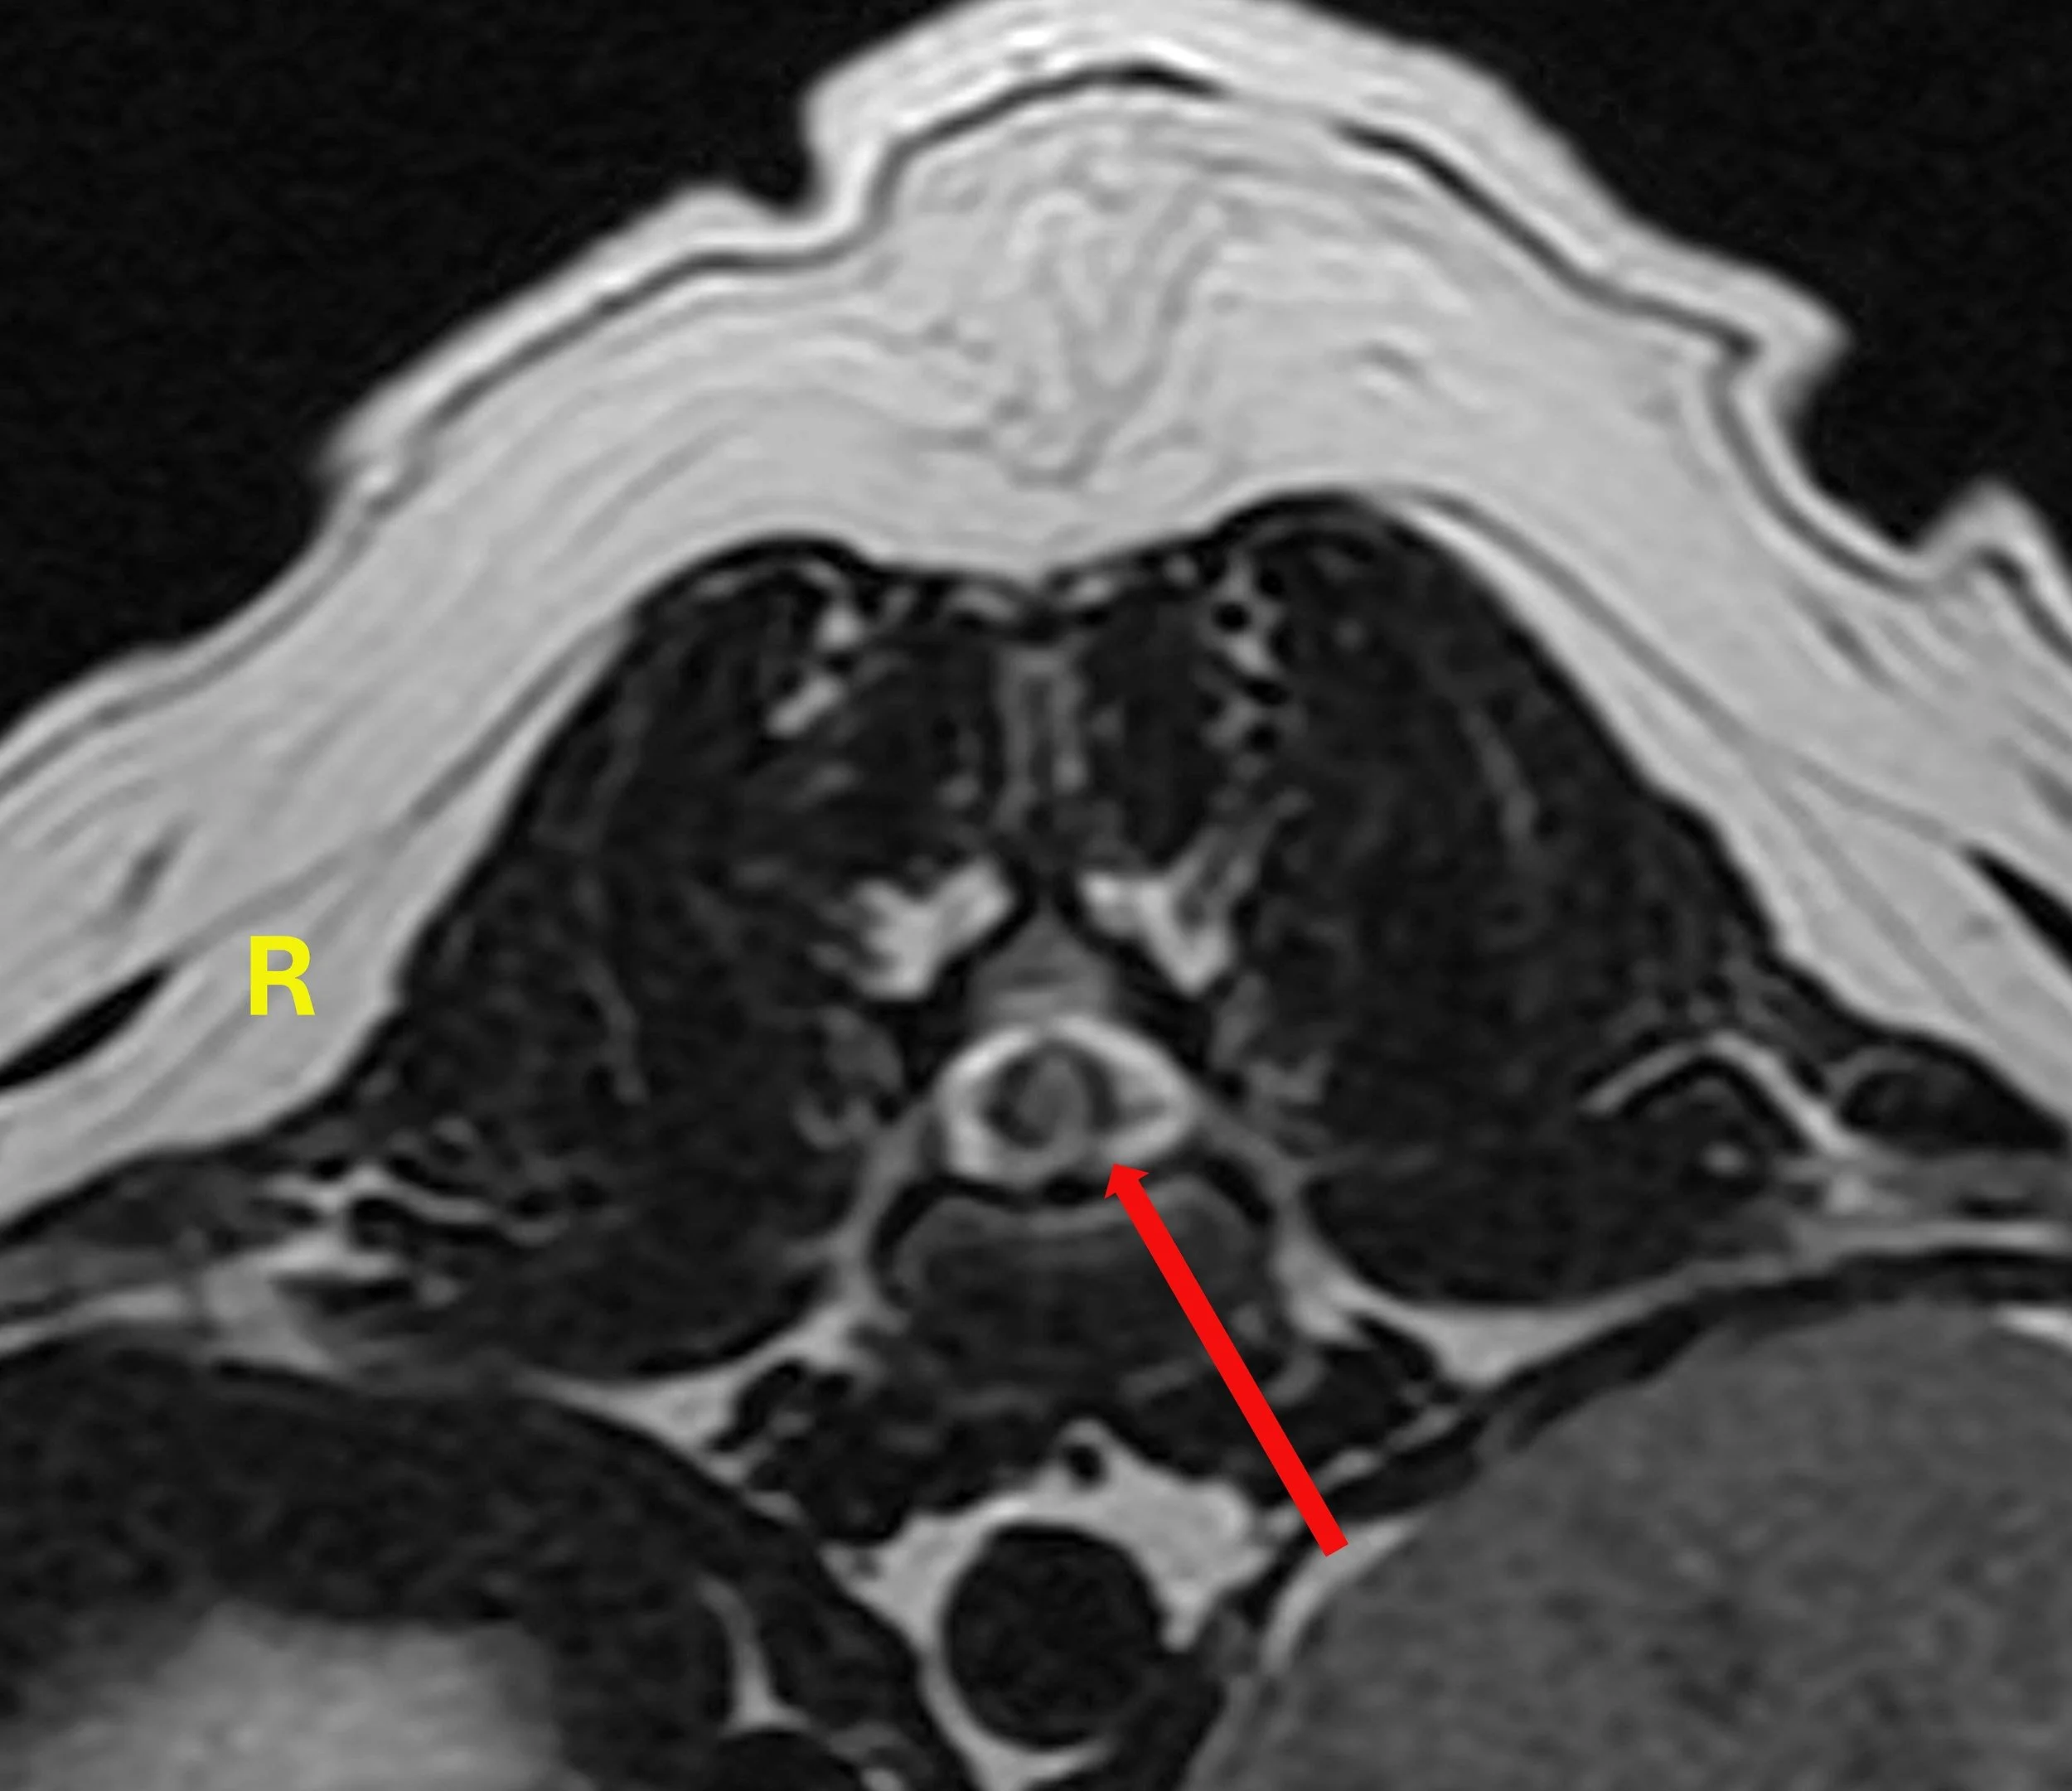

Axial view of Juno’s spine at the level of the T13-L1 disk space - MRI T2W sequence. The red arrow points towards the bright spot on the left side of the spinal cord (left and right projections are opposite in imaging figures).

Axial view of patient’s spine at the level of the T13-L1 disk space - MRI T2W sequence. The red arrow points towards the bright spot on the left side of the spinal cord (left and right projections are opposite in imaging figures).